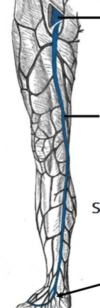

Vad är det här för vener?

v. saphena magna löper medialt i benet. Tömmer sig i låret i v. femoralis

Vilken ven från underbenet är det som tömmer sig i v. poplitea?

v. saphena parva lateralis

- börjar på fotryggen från den laterala grenen av arcus venosus dorsalis pedis –> löper på m. gastrocnemius —> löper lateralt och posteriort i benet —> tömmer sig i v. poplitea i knä.